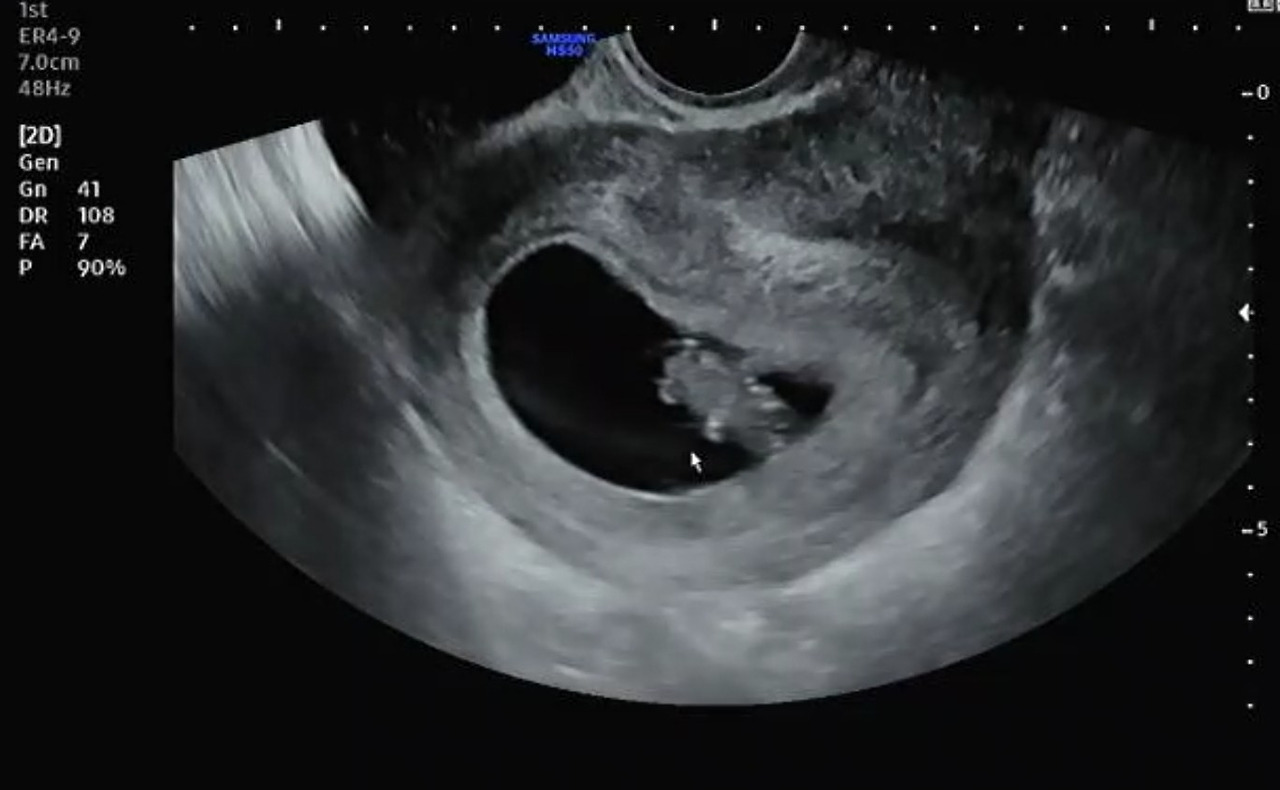

임신 8주 차 3일째가 되는 날, 산부인과를 다시 방문했다. 2주 지나서 재 내원한 산부인과는 여전히 새롭기만 했다. 병원을 방문하기 전까지 가끔 느껴지는 아랫배 통증에 걱정이 돼 인터넷 글을 검색하며 오늘의 초음파를 예상했었다. 지난 초음파에서는 아기집과 난황밖에 보이지 않아서 아쉬웠는데 이번에는 젤리 곰의 형태를 볼 수 있다는 사실이 너무 기대가 되었다.

아직 극초기라서 질초음파로 태아의 상태를 확인하기로 하고 침대에 누워 준비한다. 오늘은 다행히 남편도 뒤따라 들어와 함께 초음파를 보기 위해 대기했다.

곧이어 의사가 들어와 초음파를 확인하면 아기집에 2주 사이에 자란 태아가 '하리*'젤리의 곰 모양으로 형태를 보인다. 이전에 텅 비어 보이던 아기집에 젤리 곰 모양으로 자신의 존재를 보이는 아기가 신기하기만 했다.

가운데 심장이 뛰는 것이 보이면서 심장소리가 들려오는데, 감동적이라 살짝 눈물이 날뻔했다. 빠르면 임신 6주 차에도 심장소리를 확인할 수 있다는데 나는 이번 초음파에서 처음 확인할 수 있었다. 처음 듣는 태아의 심장소리는 말발굽 소리처럼 들려왔다. '쿠슈 쿠슈~'이런 식으로 들려오는 심장소리는 181회 뛰는 것을 확인했다. 아기는 성인과 다르게 심장이 빨리 뛰어서 이 정도 빠르기는 정상이라고 괜찮다며 의사가 설명을 했다.

초음파를 확인하며 나의 자궁이나 난소 상태를 확인하며 어느 쪽 난소에서 배란이 되어 임신이 되었는지까지 알려줬다. 다행히 내 여성기관에 혹이나 이상이 없어 보인다고 하며 아기집이 자리를 잘 잡았다고 했다.